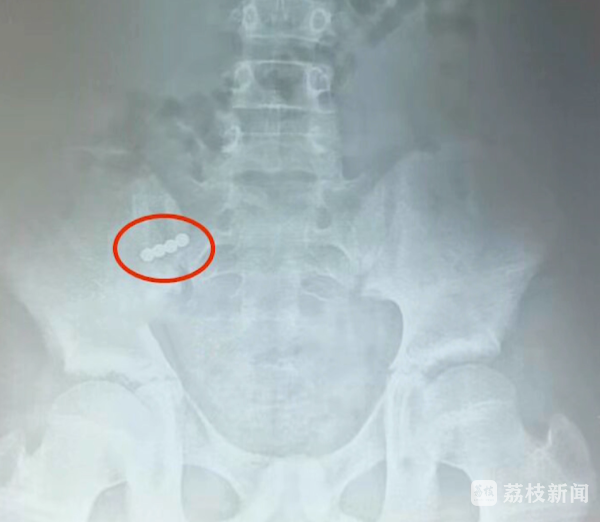

前两天,淮安市妇幼保健院为一名11岁男孩实施了手术,因为男孩误吞了4颗磁力珠,导致3处肠管穿孔。淮安市妇幼保健院小儿外科主治医师顾春晖说,当时他妈妈发现了以后,在家里面用开塞露灌肠,然后喝麻油,一天也没排下来,拍了个片子,发现4颗粘在一起。

医生根据磁力珠所处位置判断,这4颗不是同一时间吞下的,磁力珠吸力很强,彼此吸附会造成肠管粘连,引发肠管穿孔、坏死,所以必须尽快手术。顾春晖说,因为我们手术及时,他的三处穿孔没有造成大量肠内容物外泄,如果说肠内容物外泄较多的话,后期可能会形成腹膜炎,术后并发症会比较多。